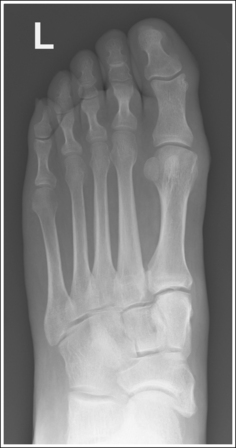

The foot demonstrates an AP projection. The joint space between the medial (first) and intermediate (second) cuneiforms is open, approximately 0.75 inch (2 cm) of the calcaneus is demonstrated without talar superimposition, and concavity on both sides of the first metatarsal midshaft is equal.

The tarsometatarsal (TMT) and navicular-cuneiform joint spaces are open.

• The bones of the foot, with their ligamentous and muscular structures, are arranged in a longitudinal arch that is visible on the medial foot surface. This arch places the tarsometatarsal and navicular-cuneiform joint spaces at a set angle with the IR. To demonstrate these joints as open spaces, angle the central ray until it is aligned parallel with them. This is accomplished in most patients by using a 10- to 15-degree proximal (toward the calcaneus) angle or aligning the central ray perpendicularly with the dorsal surface. The exact degree of angulation needed depends on the height of the longitudinal arch. A 10-degree angle should be used when the patient's longitudinal arch is low, as shown in Figure 6-15. A 15-degree angle is needed in a patient with a high arch, as shown in Figure 6-16. Higher arched patients require a slightly higher angle. Omitting or employing an inaccurate central ray angulation results in obstructed TMT and navicular-cuneiform joint spaces (see Image 14).

The third metatarsal base is at the center of the exposure field. The proximal calcaneus, talar neck, tarsals, metatarsals, phalanges, and surrounding foot soft tissue are included within the collimated field.

• To place the third metatarsal base in the center of the image, center the central ray to the midline of the foot at a level 0.5 inch (1.25 cm) distal to the fifth metatarsal tuberosity. The fifth metatarsal tuberosity can be palpated along the lateral foot surface, approximately halfway between the ball of the foot and the calcaneus.